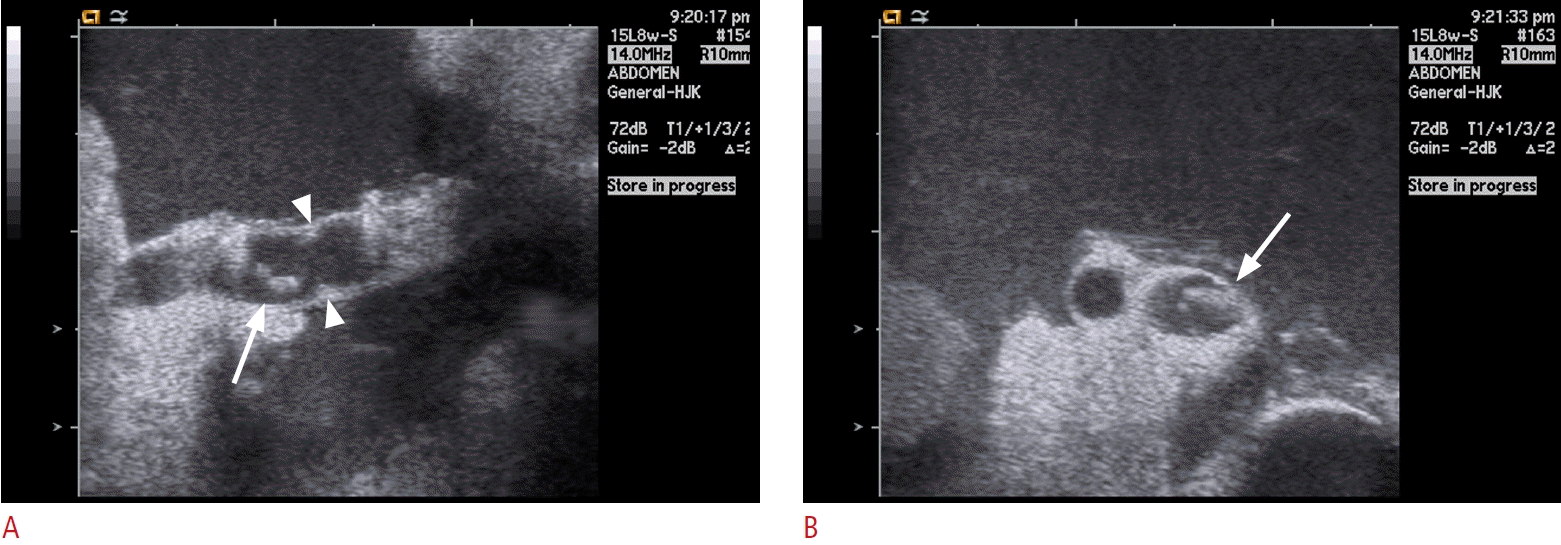

Fig. 9.

Thrombus in interposed venous conduit.

A, B. Grayscale (A) and color Doppler (B) intraoperative ultrasonograms of the middle hepatic vein tributary in segment 8 (V8) and interposing venous conduit, show echogenic intraluminal thrombus (arrows) and color signal void. C. Axial computed tomography scan obtained during hepatic arterial phase on postoperative day 1 demonstrates nonopacification of V8 (arrowheads) and well-demarcated, wedge-shaped area of hypoattenuation (arrows) in right anterior sector that corresponds to draining territory of V8. Vertex of wedge-shaped low attenuation area typically points to inferior vena cava. D. Hepatic venography reveals intraluminal thrombus of the middle hepatic vein tributary in V8, seen as filling defect (arrows). Endovascular stent placement was performed.

HV complications are relatively common in LDLT with modified right-lobe graft. IOS visualize anastomotic site directly and hemodynamic effect by changes in flow velocity and waveform [19]. Pathologic state that compromises the HVs produce a dampening of the Doppler tracing, with loss of various component of the normal triphasic pattern (Fig. 8). There has been controversy regarding as the relationship between the HV velocity within the graft and anastomotic stenosis [12,20]. Particularly in MHV tributaries and interposition vein graft, there are tendency of very rapid thrombus formation with flow stasis. Thrombus may appear as echogenic filling defect within the lumen in IOS (Fig. 9) [21].